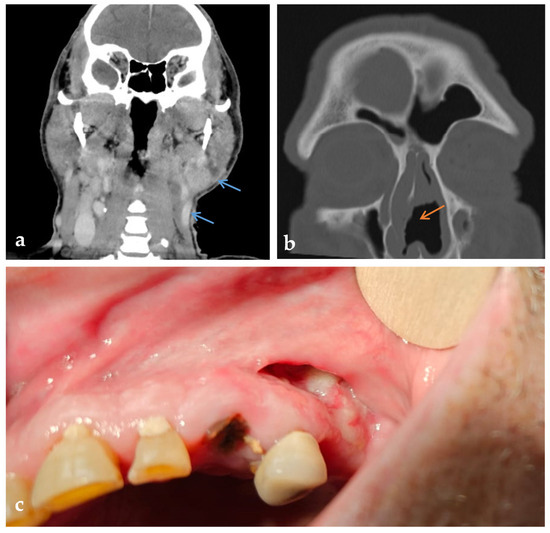

In April 2025, he was hospitalized again due to the deterioration of the local findings and his general condition. The ulcerations became larger, deeper, and confluent, turning into a wide wound with purulent contents and signs of acute infection. The CRP level was 226 mg/L, and the hemoglobin level was 103 g/L (reference 138–175 g/L). A newly developed perforation of the nasal septum with a diameter of about 2 cm was discovered as well as an ulceration in the area of the upper vestibular region on the left side of the oral cavity (Figure 3). A subsequent CT scan of the head, neck, and thorax showed progression—the submandibular lesion enlarged to 32 mm (previously 10 mm) with invasion of the skin at the level of the hyoid bone and progressive thickening of the mucosa of the oral cavity with extension into the nasopharynx and oropharynx (Figure 3). The wound swabs remained sterile, and Streptococcus mitis/oralis was isolated from the ulcer in the oral cavity, which was interpreted as a commensal bacterium. Urine toxicology was positive for cocaine, which the patient subsequently confirmed—with chronic intranasal use. Bronchoscopy showed no evidence of trachea, bronchi, or lung involvement. BAL was negative for infection, and pigmented macrophages were present. Cardiac ultrasound showed no signs of endocarditis. Systemic therapy with methylprednisolone (0.5 mg/kg) and a combination of meropenem and vancomycin for suspected concomitant bacterial infection was initiated. The therapy led to an improvement in the local findings and a decrease in the inflammatory parameters (Figure 1). The day before discharge, the patient experienced an episode of vomiting and drowsiness, which resolved after symptomatic treatment. The interview confirmed acute benzodiazepine intoxication. The patient was discharged hemodynamically stable, afebrile, and in an improved clinical condition. The PR3-ANCA level at this time was 49 U/mL (reference < 5 U/mL).

Figure 3. Radiologic and intraoral findings in PR3-ANCA-positive cocaine-induced vasculitis (CIV). (a) Coronal contrast-enhanced CT showing soft tissue lesions with increased enhancement in the left supraclavicular and parotid region (blue arrows). (b) Axial CT of the paranasal sinuses with perforation of the nasal septum (orange arrow). (c) Intraoral view showing mucosal ulceration and exposed bone in the upper left oral vestibule.